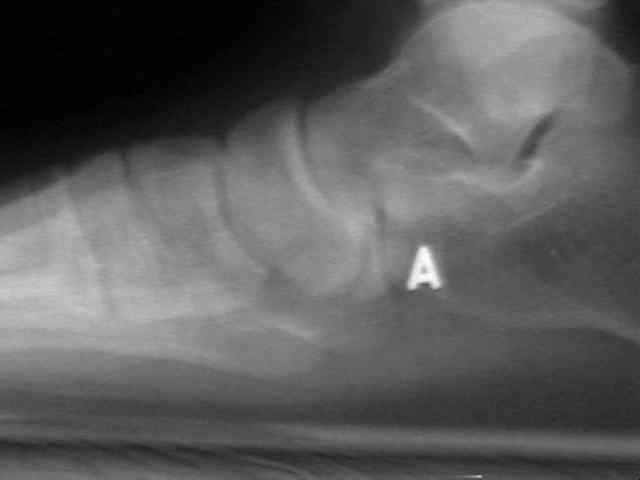

Radiographs

• radiographs may not be helpful if the accessory ossification is not ossified;

• the standard oblique of the foot (medial internal oblique view) will not show the accessory ossicle in profile;

• the lateral (external) oblique view is the radiograph of choice;

• although accessory navicular appears distinct from the navicular on x-rays, it is actually attached by fibrous tissue or cartilage;

Accessory Navicular 2 Accessory Navicular 3 Accessory Navicular 4